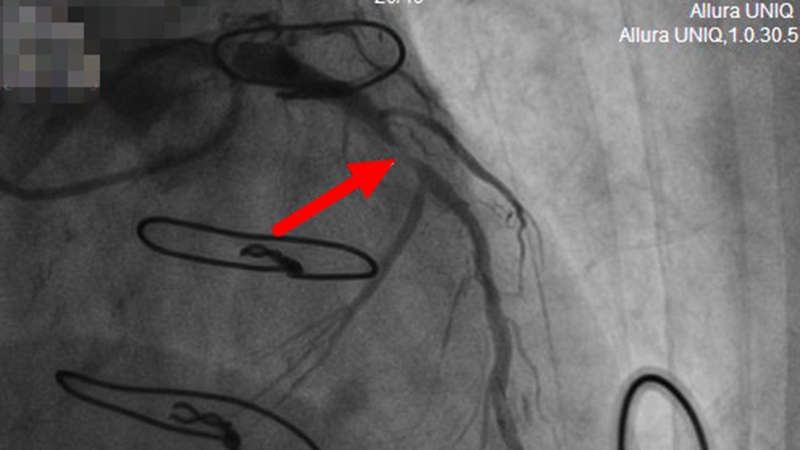

【术前,前降支近段严重狭窄】